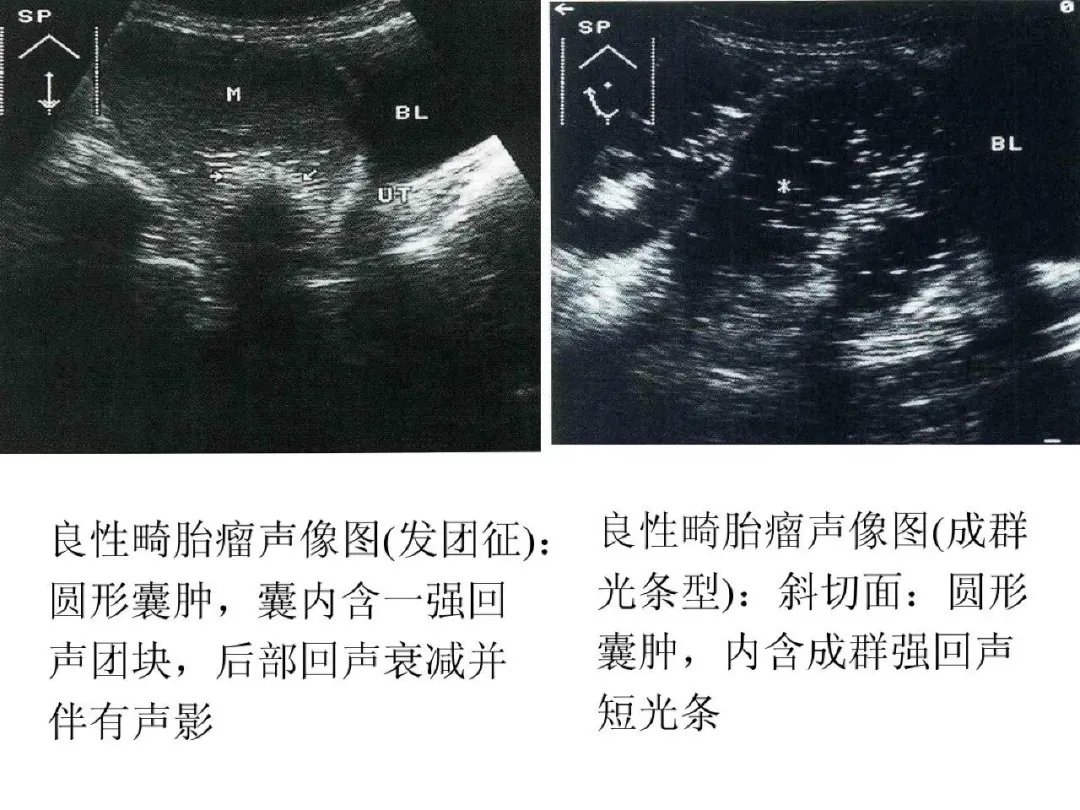

●良性畸胎瘤超声特点:圆形或椭圆形,多为单侧;壁厚,清晰或不清;囊内显示飘浮光点,如面团征、发团征、脂液分层征;内可显示强回声光团、光带。

●声像图特征:肿瘤较大,呈圆形、椭圆形或欠规则;瘤壁厚;内部回声较复杂,可出现脂液分层,强回声光团或低回声实性区;内部血流较丰富。